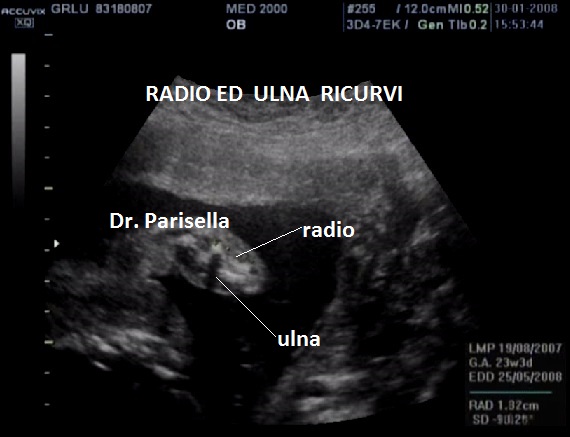

tibia ricurva

radio ricurvo

ulna curva

fibula curva